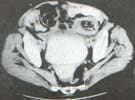

Una nueva colonoscopia mostró hallazgos similares a la anterior y una vez más las biopsias no fueron conclusivas. Se practicó entonces una TAC abdominal en la cual se observó un ensanchamiento anormal concéntrico del colon descendente y neumatosis coli, sugestiva de una lesión isquémica o inflamatoria.

Adicionalmente se encontró la presencia de una masa polipoide de bajo grado de atenuación (densidad de grasa), en posición intraluminal a nivel del colon descendente. Con estos hallazgos se sugirió como diagnóstico una Intususcepción Colo-cólica del Colon Descendente a partir de un pólipo intraluminal (Figura 1).

Figura 1. Tomografía axial computarizada del abdomen con doble contraste en

la que se aprecia una masa de aproximadamente 2 x 3 centímetros, de baja

densidad, dentro de la luz del colon descendente (1). Adicionalmente se

observa edema importante de la pared del colon, proximal al sitio donde se

observa la masa descrita. La grasa intraluminal a nivel del segmento de

colon corresponde al mesenterio del colon con intususcepción (2)